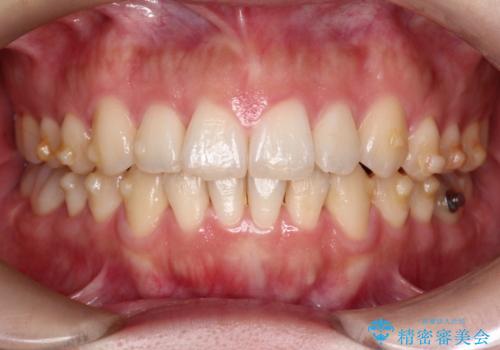

【インビザライン】前歯の凸凹を治したい

- 前歯の凸凹を主訴に来院されました。

インビザラインにて臼歯部の遠心移動を行いながら、できるだけ前歯が出ないように気を付けて治療を行っています。

遠心移動を行う必要があったので、患者様には顎間ゴムを使用していただきました。